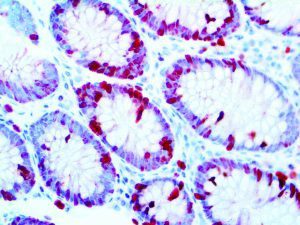

The first cytokines released are interleukin 1β (IL-1β) and tumor necrosis factor-α (TNF-α), which attract a variety of circulating white blood cells (WBCs) to the infection site, including neutrophils, monocytes, macrophages, and natural killer (NK) cells. This response, along with the antipathogenic chemicals released by these cells (i.e., complement), comprise the innate immune response. These cells directly attack the invading pathogen and also release additional cytokines, chief among them interleukin-1 and 6 (IL-6). IL-6 is essential for invoking the adaptive immune response, which calls T-cells, B-cells, and T helper (Th) cells to the infection site. IL-6 also stimulates further recruitment, proliferation and activation of macrophages.

It is the ICU physician who is most likely to witness one of the deadliest manifestations of the abnormal immunological response, the cytokine storm syndrome (CSS). This response is also referred to by some as the cytokine release syndrome (CRS). CSS is characterized by continuous activation and expansion of macrophage and lymphocyte populations, which secrete large amounts of cytokines, causing the cytokine storm. This massive cytokine release is akin to hemophagocytic lymphohistiocytosis (HLH) disease, a syndrome characterized by initial unchecked and persistent activation of cytotoxic T lymphocytes and NK cells.